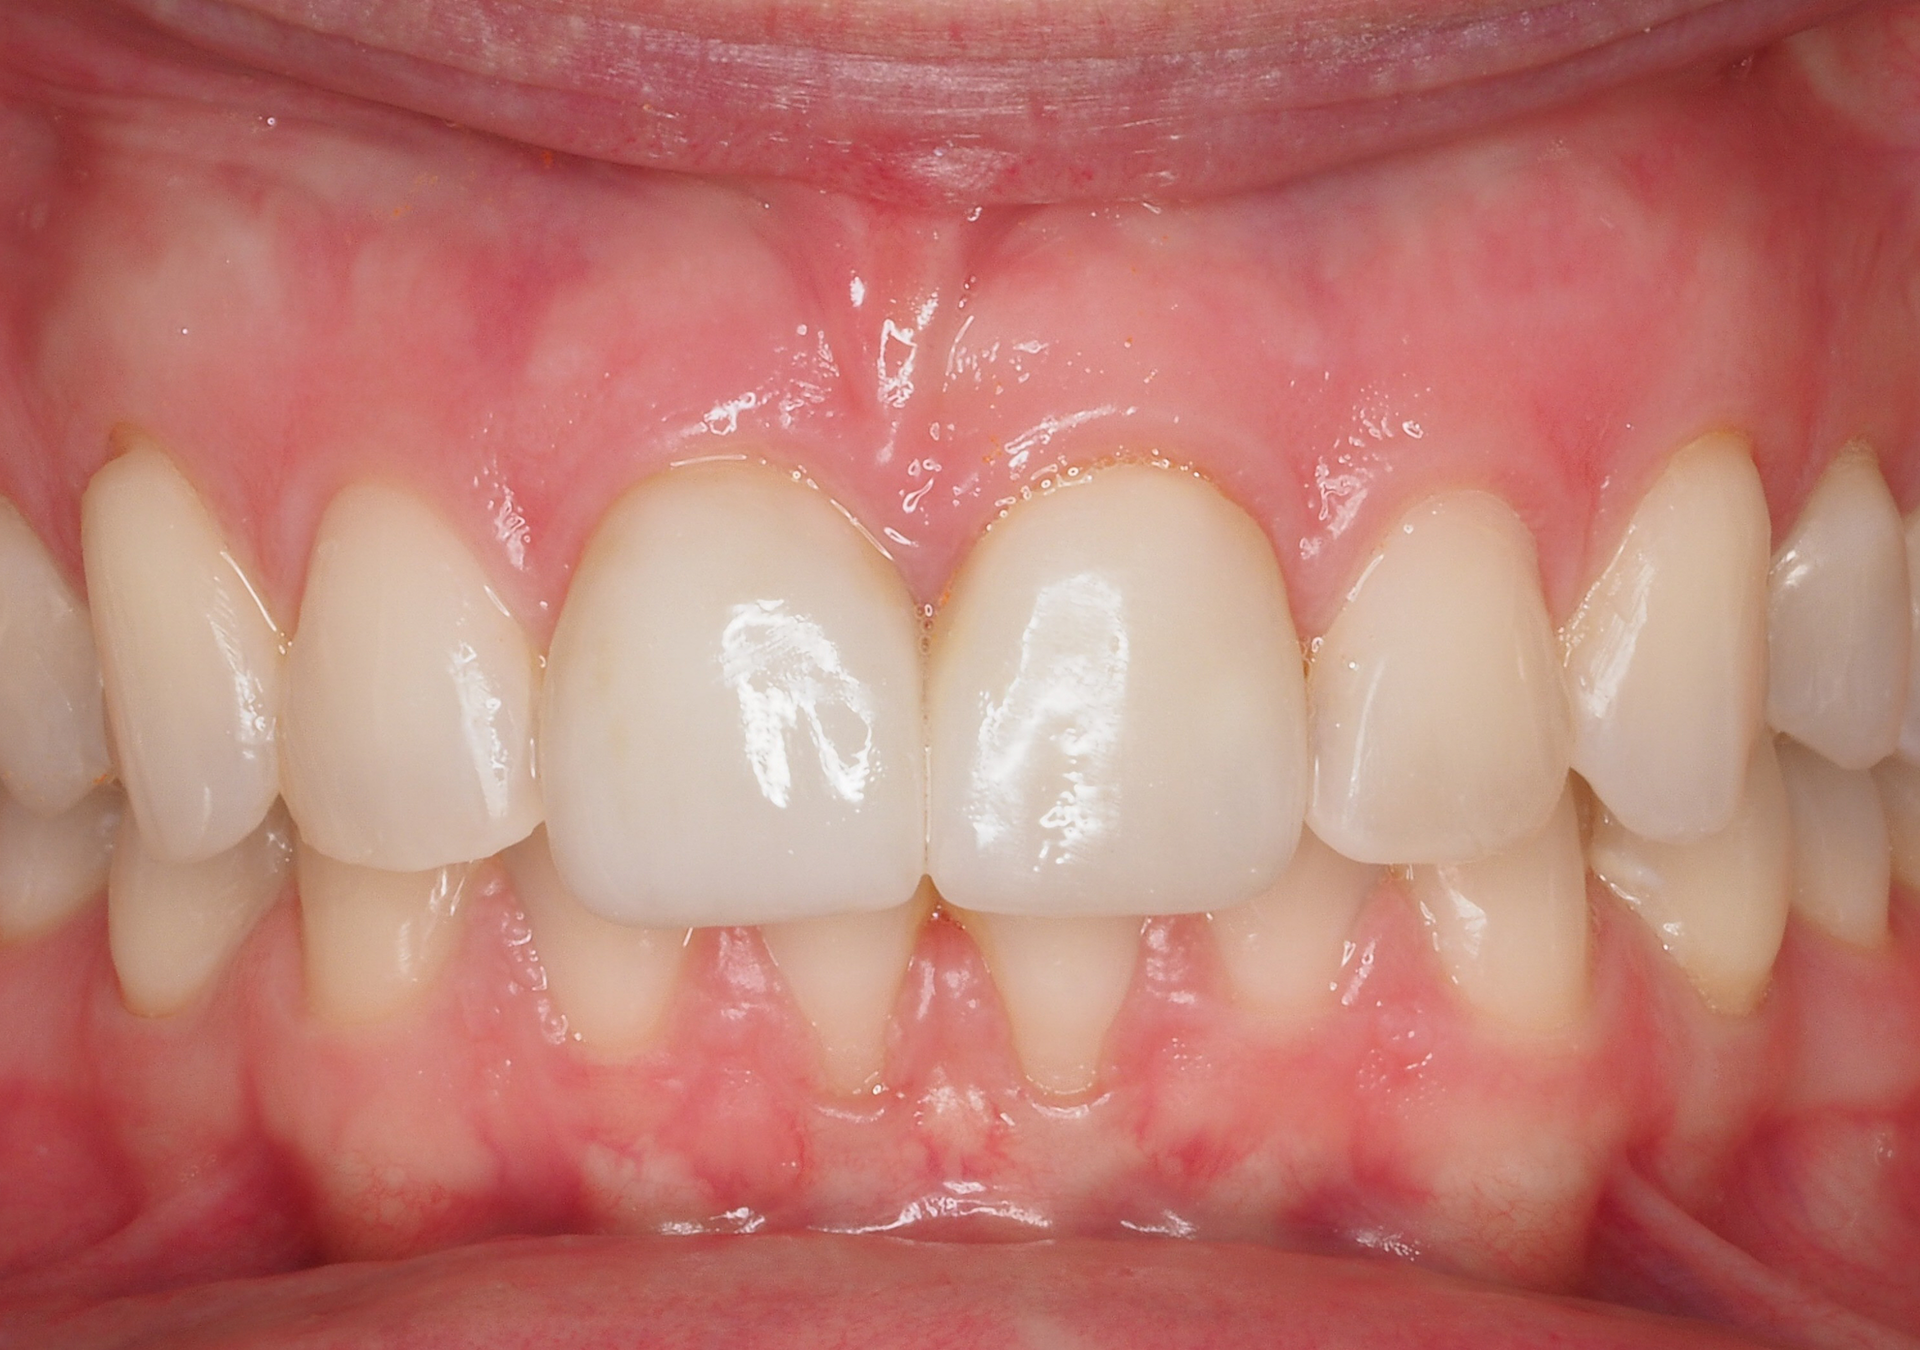

- 25 años de experiencia en restauraciones de resina composite tanto en sectores anteriores como posteriores.

- Resultados estéticos comparables a la cerámica, de larga durabilidad.